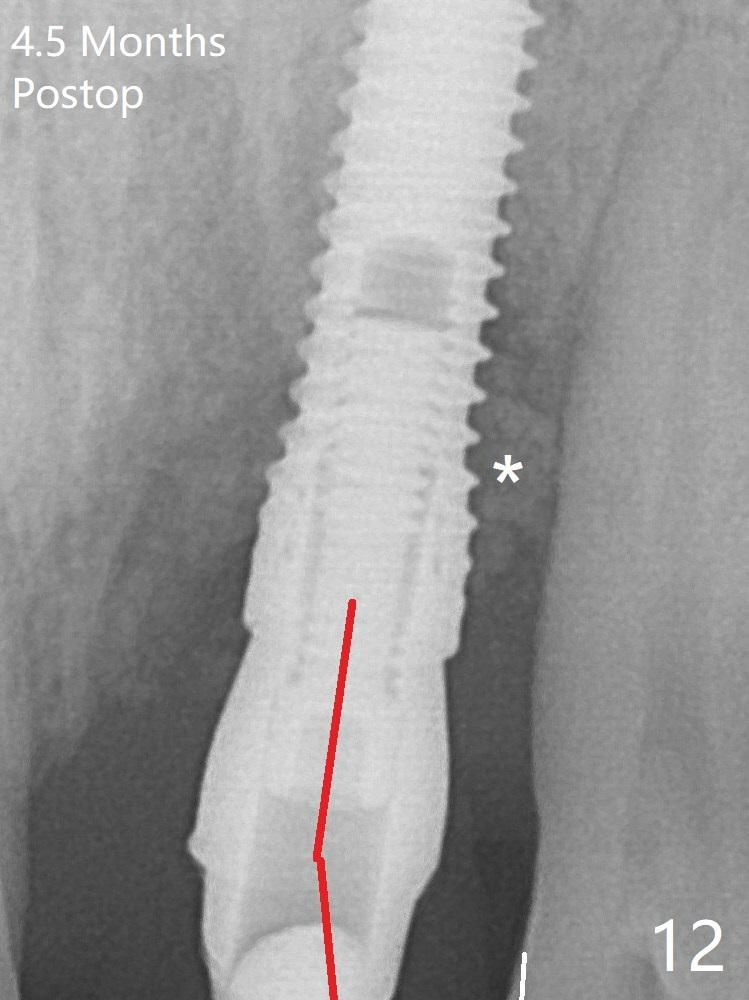

After placement of a 3.8x15 mm implant, PRF is laid against the inner surface of the buccal defect and allograft (Fig.5 *) is packed mainly in the buccal gap before and after insertion of a 4.5x5(4) mm abutment. The bone graft remains in place 3.5 and 4.5 months postop (Fig.11,12 *). Between 3 and 4 months postop, the mesial surface of the abutment has been trimmed (Fig.12 >). Since the mesial surface of the tooth #10 will be reduced (white curved line) to correct the upper dental midline, an angled abutment (red line) seems to be necessary to shift the provisional distal. The socket at UL1 seems to have healed except the most coronal 1 year 3 months postop (Fig.14 *).